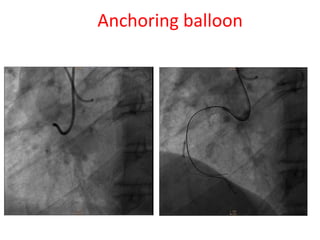

This document discusses various techniques for improving support during transradial catheterization procedures, including using guide catheters with backup support, extra-support guidewires, buddy wires, larger 7-8 French guide catheters, anchoring balloons placed in branches, deep intubation of guide catheters, and guide catheter extensions. It provides guidance on how to select the appropriate technique based on the vessel accessed and level of support needed.